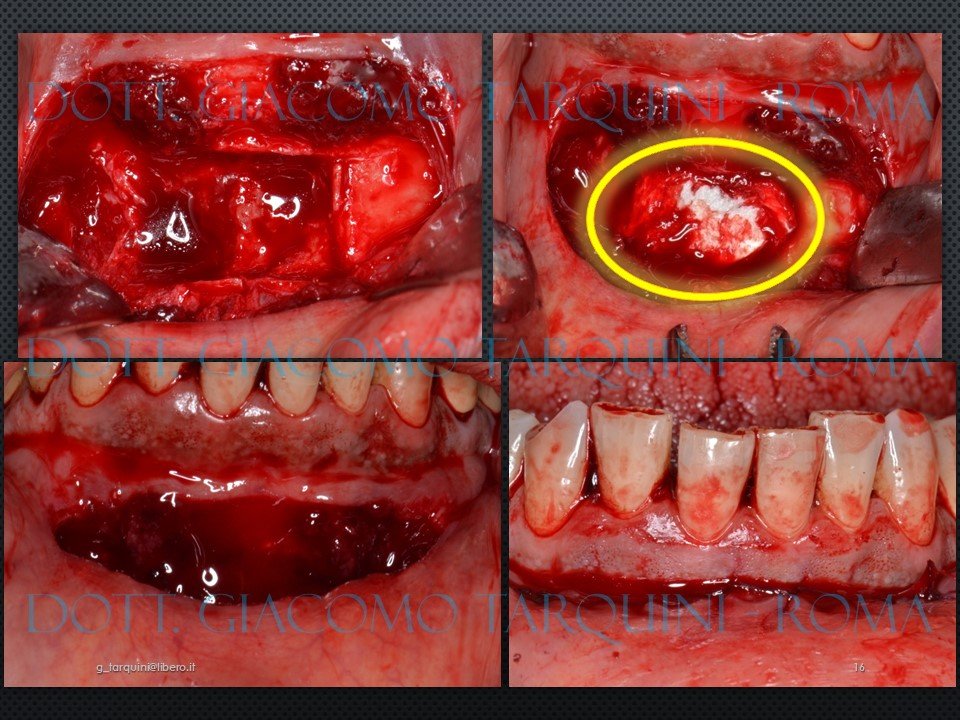

Il presente caso clinico descrive il protocollo chirurgico per il trattamento di un'atrofia mascellare di "Classe D" secondo la classificazione proposta da Chiapasco (Chiapasco, COIR 2008) consistente in un rialzo del seno mascellare per via laterale associato a un innesto di osso autologo in blocco prelevato dalla sinfisi mentoniera.

Diapositiva16.JPG.898a618edad372febf4367688ba7cca8.JPG